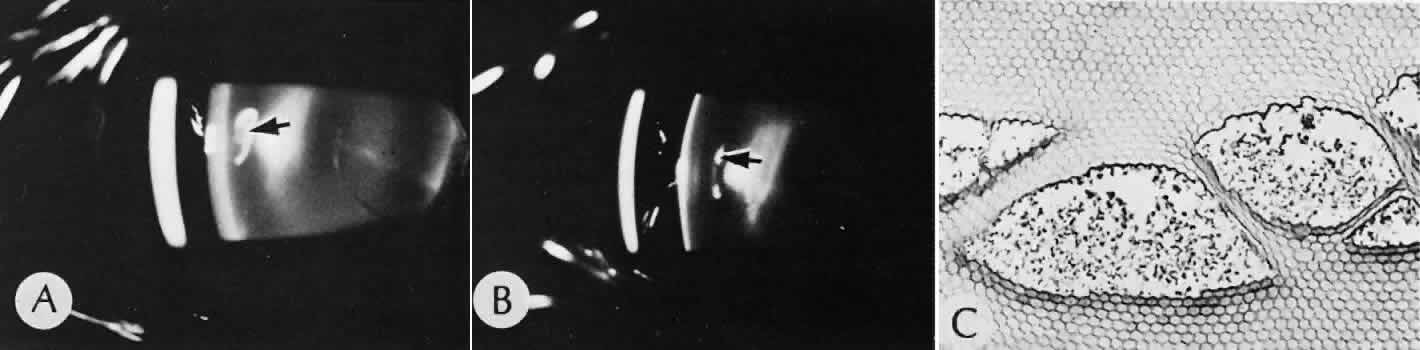

With several microkeratomes, scanning electron microscopy may show a fine undulating contour up to 0.2 mm at the border of the lamellar bed and flap. This feature is formed as chatter lines parallel to the cutting edge of the microkeratome blade (Fig. 19). The frequency of the chatter may relate to the nonlinear pass of the microkeratome. Chatter is absent in rotary keratomes and keratomes using a high oscillation frequency.66–68

Fig. 19. Scanning electron microscopy of the lamellar bed in LASIK. A. At the edge of the wound, oscillation marks caused by some types of microkeratome can be identified. B. The lamellar bed in the center of the wound is moderately irregular.